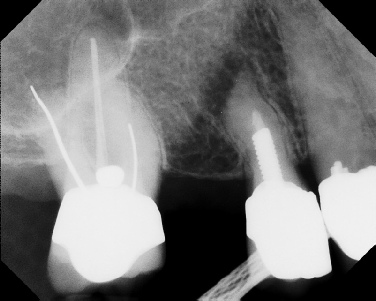

COMPLICATED ANATOMY LARGE LESIONS CALCIFIED CANALS PERFORATION / RESORPTION SEPARATED INSTRUMENTS SURGICAL CASES RETREATMENT / pOST REMOVAL OPEN APICES ACCESS THRU CROWNS Root Canal Case Portfolio

Apicoectomy - Surgical Root Canal Pre-op (post trauma) Coronal segments obturated Apical segments surgically removed 3 years